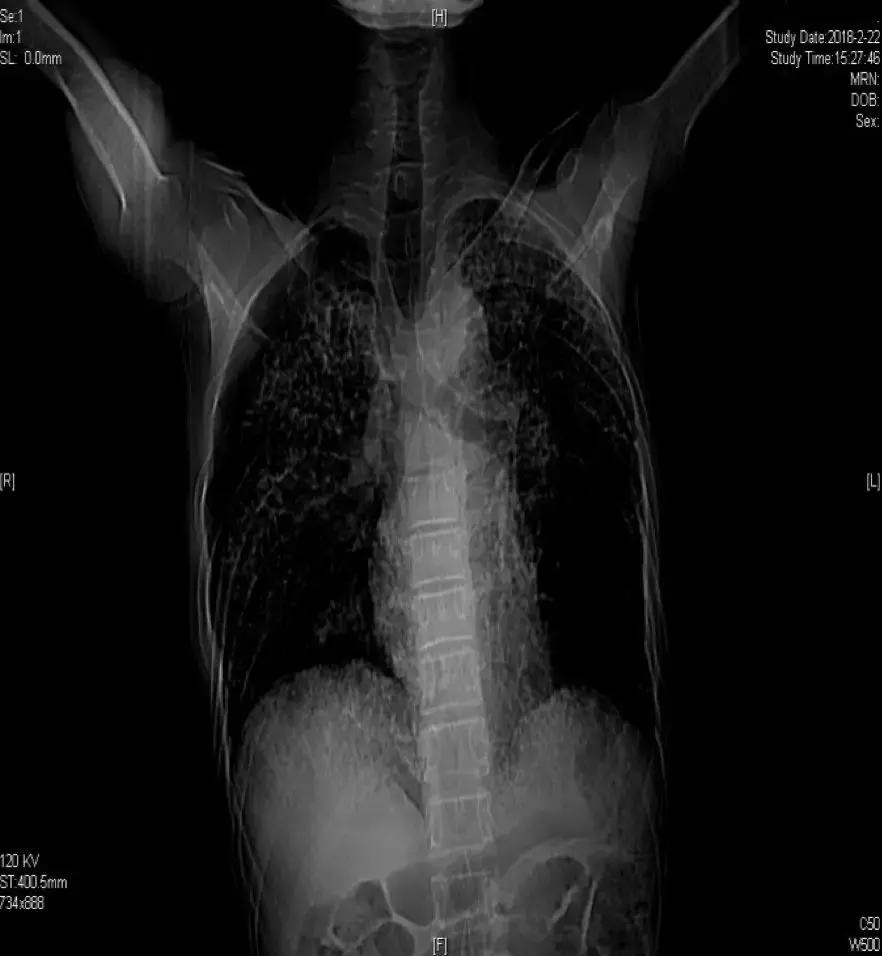

胸部CT(2017-07-11):

胸部CT(2018-02-22):